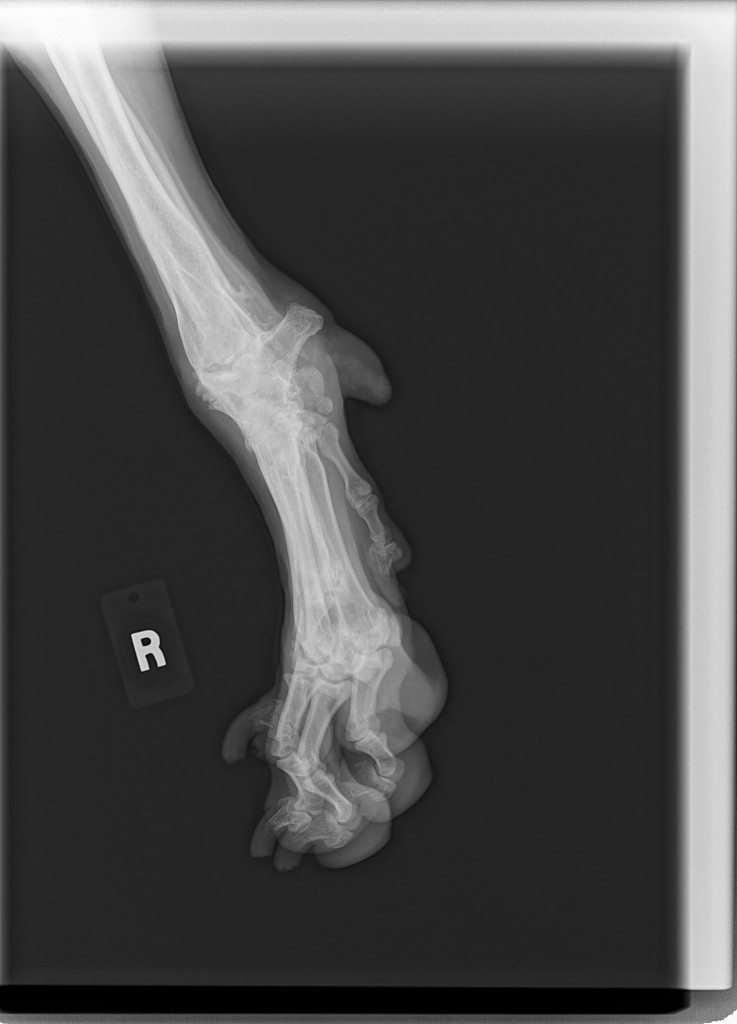

Sean has been diagnosed with a retro-peritoneal liposarcoma.

The current size of his mass is 8.2 cm x 10 cm x 21 cm. This is an extremely RARE cancer – less than 1%.

To further complicate matters, this mass has herniated down into his thigh and groin severely compromising his ureter and femoral nerve. He has had three CT scans of which his latest has shown that to date his chest remains clear of metastasis and his lymph nodes are not enlarged. His MRI has shown that his case is extremely complicated and the surgery he shall specifically require, scheduled for March 23rd has ONLY ever been done twice before by the two expert surgical oncologists assigned to him.